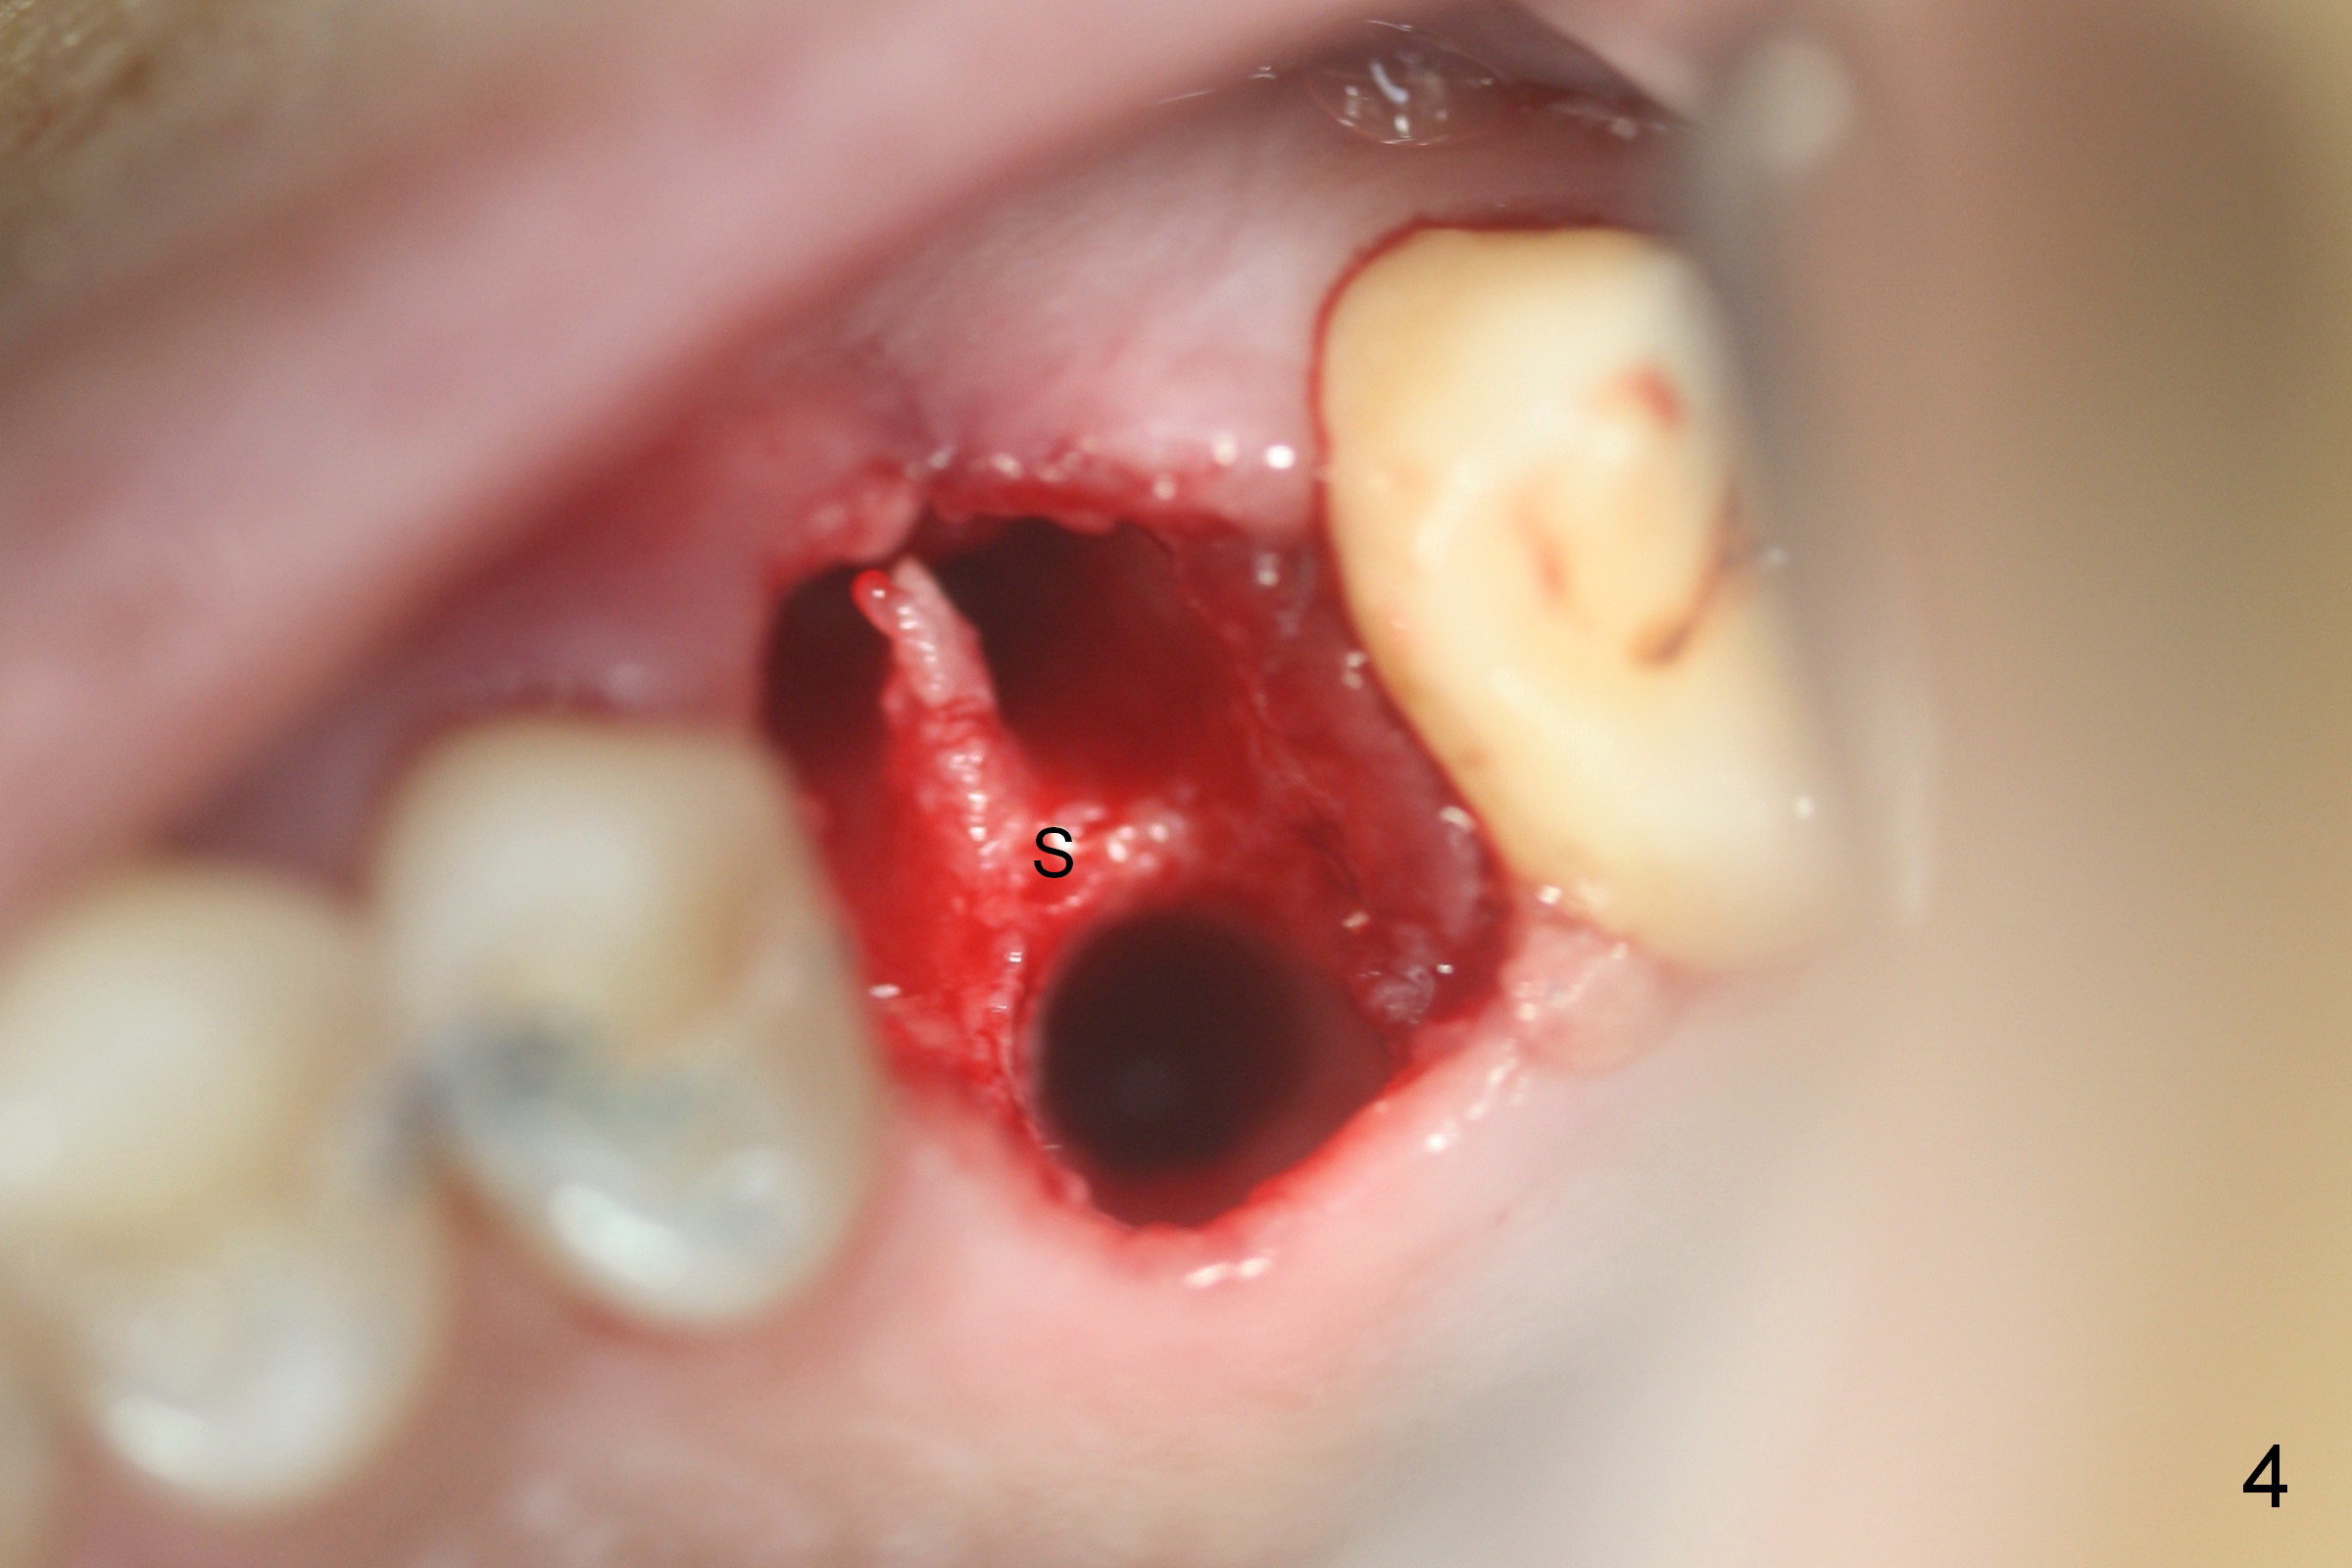

Preop CT shows that the septum appears to be able to hold a 11 mm long implant (Fig.1 sagittal section). There are periapical radiolucent lesions of the buccal (Fig.2 (coronal section) B) and palatal roots; bone height above the buccal apex is ~ 2 mm (Fig.3). When the tooth #14 is extracted, a 1.6 mm pilot drill is used to start osteotomy in the middle of the fairly thin septum (Fig.3 red line, Fig.4 S). It is hoped that Magic Expanders (ME) can enlarge the osteotomy by pushing the buccal and palatal bone plates of the septum outward (Fig.5 arrows).

The septal bone is dense and the osteotomy is enlarged by alternating use of drills and expanders. By the time 3.8 mm ME is tapped in (Fig.6), the buccal plate of the septum is perforated. The ME is stable, in spite of the fact that it is only supported by 2-3 mm bone buccally (Fig.7). Continuously alternating use of MEs and drills leads to placement of a 5x11 mm implant with 30 Ncm insertion torque and sinus lift. After placement of bone graft (Fig.8 *) and 5x4(3) mm pair abutment (A), an immediate provisional is fabricated. Red dashed lines in Fig.6,9 represent the mesial outline of the socket, whereas black dashed in Fig.6 sinus floor. It suggests that the implant is stabilized by relatively small amount of native bone. Although IBS implants have aggressive thread patterns, a proper apical osteotomy should be prepared in the depth (perforates the sinus floor in this case) and diameter (4.3 mm drill) prior to placement.